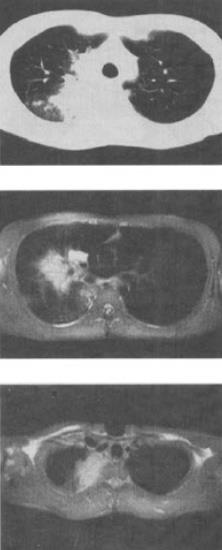

- 单项选择题 患者男,28岁,咳嗽,咯血,消瘦盗汗1个月余,影像学检查如图,最可能的诊断为()。

- C